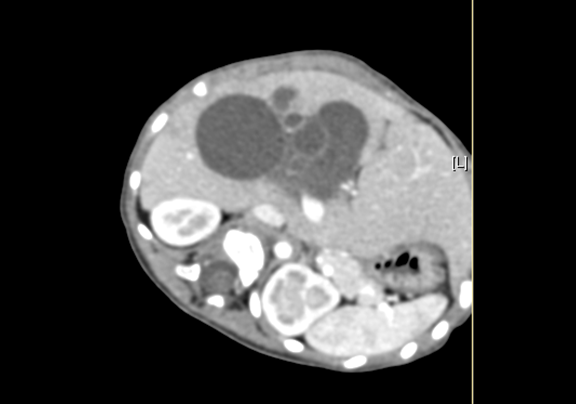

术前CT检查:

平衡期

上腹部增强CT:符合胆总管囊肿。

将0.625mm双源薄层CT资料的静脉期和动脉期Dicom格式文件导入海信CAS系统。

通过调节窗宽窗位调整CT序号,对肝实质,胆囊,胆总管,下腔静脉,肝动脉、门静脉及肝静脉等进行三维重建;系统自动计算肝脏体积。